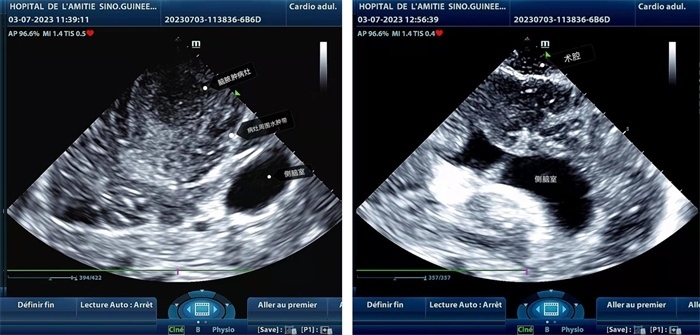

左圖顯示術中超聲見囊實性病變,大小約為4x4x3cm,病灶周圍腦組織水腫明顯;右圖為病灶切除后,術中超聲示術腔無病變殘留

左圖顯示術中超聲見囊實性病變,大小約為4x4x3cm,病灶周圍腦組織水腫明顯;右圖為病灶切除后,術中超聲示術腔無病變殘留。中國第二十九批援幾內亞醫(yī)療隊供圖

手術中,張國濱在超聲科顧秀娟的幫助下,運用顱腦術中超聲技術,通過將一次性保護套的超聲探頭置于腦組織表面,實時觀察病變的位置和形態(tài),進一步確認最佳手術路徑。術中超聲顯示,病變位于左額頂葉,大小約為4x4x3cm,邊界清晰,呈囊實性,周邊腦組織水腫明顯。最終,病灶順利切除,診斷為腦膿腫,并通過超聲檢測確認術腔無病變殘留、無出血,為患者術后恢復提供了良好的保障。